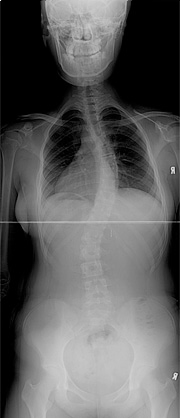

특발성 척추측만증 수술전